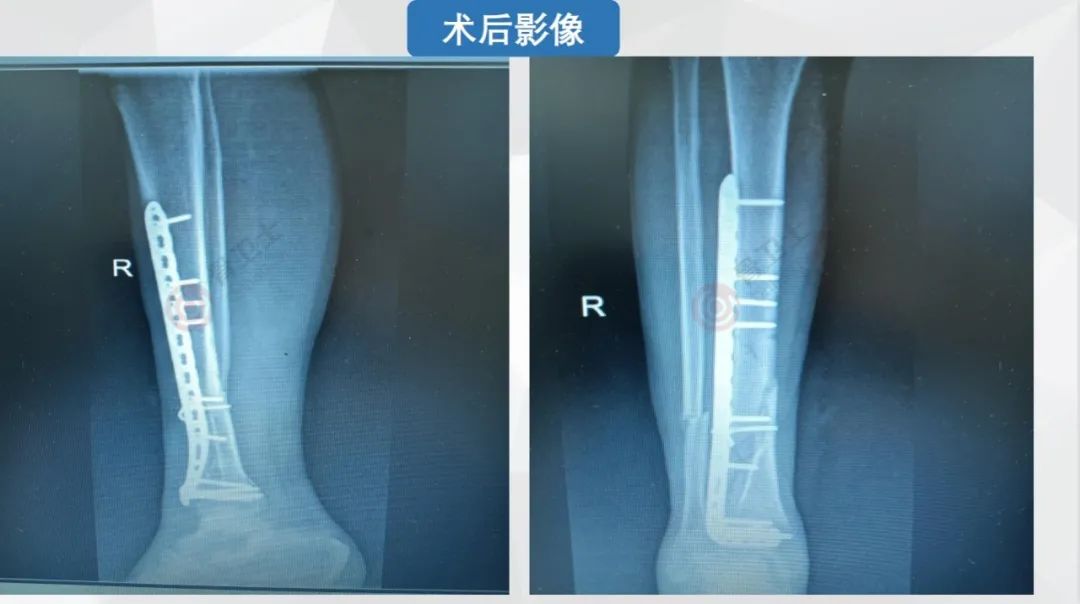

640 (33).jpg

▲患者术后影像